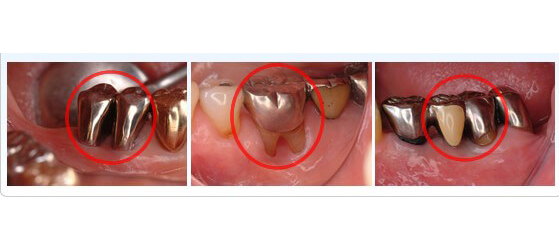

複雑に枝分かれした歯根形態に注目

インプラント治療の対象部位を見てみると前歯に比べ奥歯の頻度が多いのが現状です。では何故奥歯を失う患者様が多いのでしょうか?その大きな原因の一つとして奥歯特有の複雑な解剖学的形態が挙げられます。

図に示した様に、前歯は歯根が1本であるのに対し奥歯の歯根は殆どが複数本でその形態も複雑です。正確なブラッシングも難しく、また歯周病(細菌感染)が一旦歯の周囲に拡大すると確実な細菌の除去が難しくなります。

抜歯以外の選択肢

感染の入口である分岐部の狭さにも注目

その難しさ故に早期に抜歯→インプラント治療も一つの治療方法ではありますが、その前に即抜歯ではなく奥歯の一部分を抜去・分割等することにより、歯周病治療が可能となり、ひいてはその歯の保存も可能な場合があります。その1部をご覧ください。

歯の1部分を抜去することにより感染拡大を未然に防ぐことが可能です。

歯間ブラシ等磨き易い形態に治療・修正することも可能です。

以上示した治療例は、全て術後約10年間機能しております。